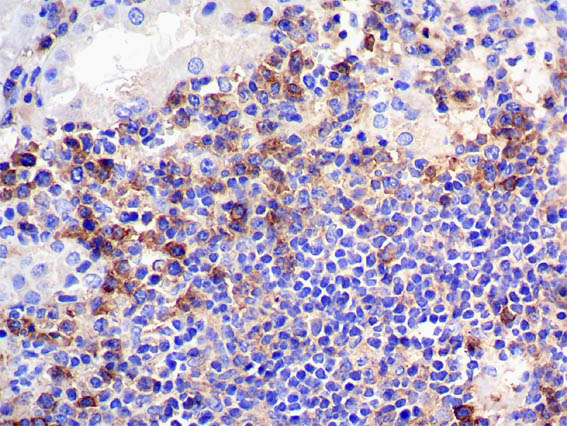

Figure 12. Immunohistochemistry for CD38, X400.